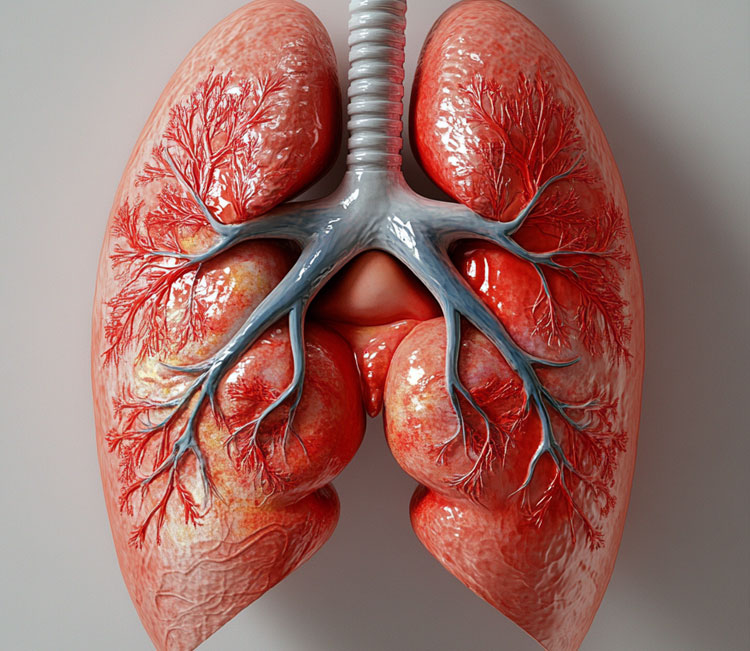

CollectiveX AI: Revolutionizing Medical Diagnosis and Treatment Planning

Discover how CollectiveX's AI-powered platform is enhancing diagnostic accuracy and treatment planning. By combining global medical expertise with advanced artificial intelligence, we're improving patient outcomes and revolutionizing healthcare delivery.